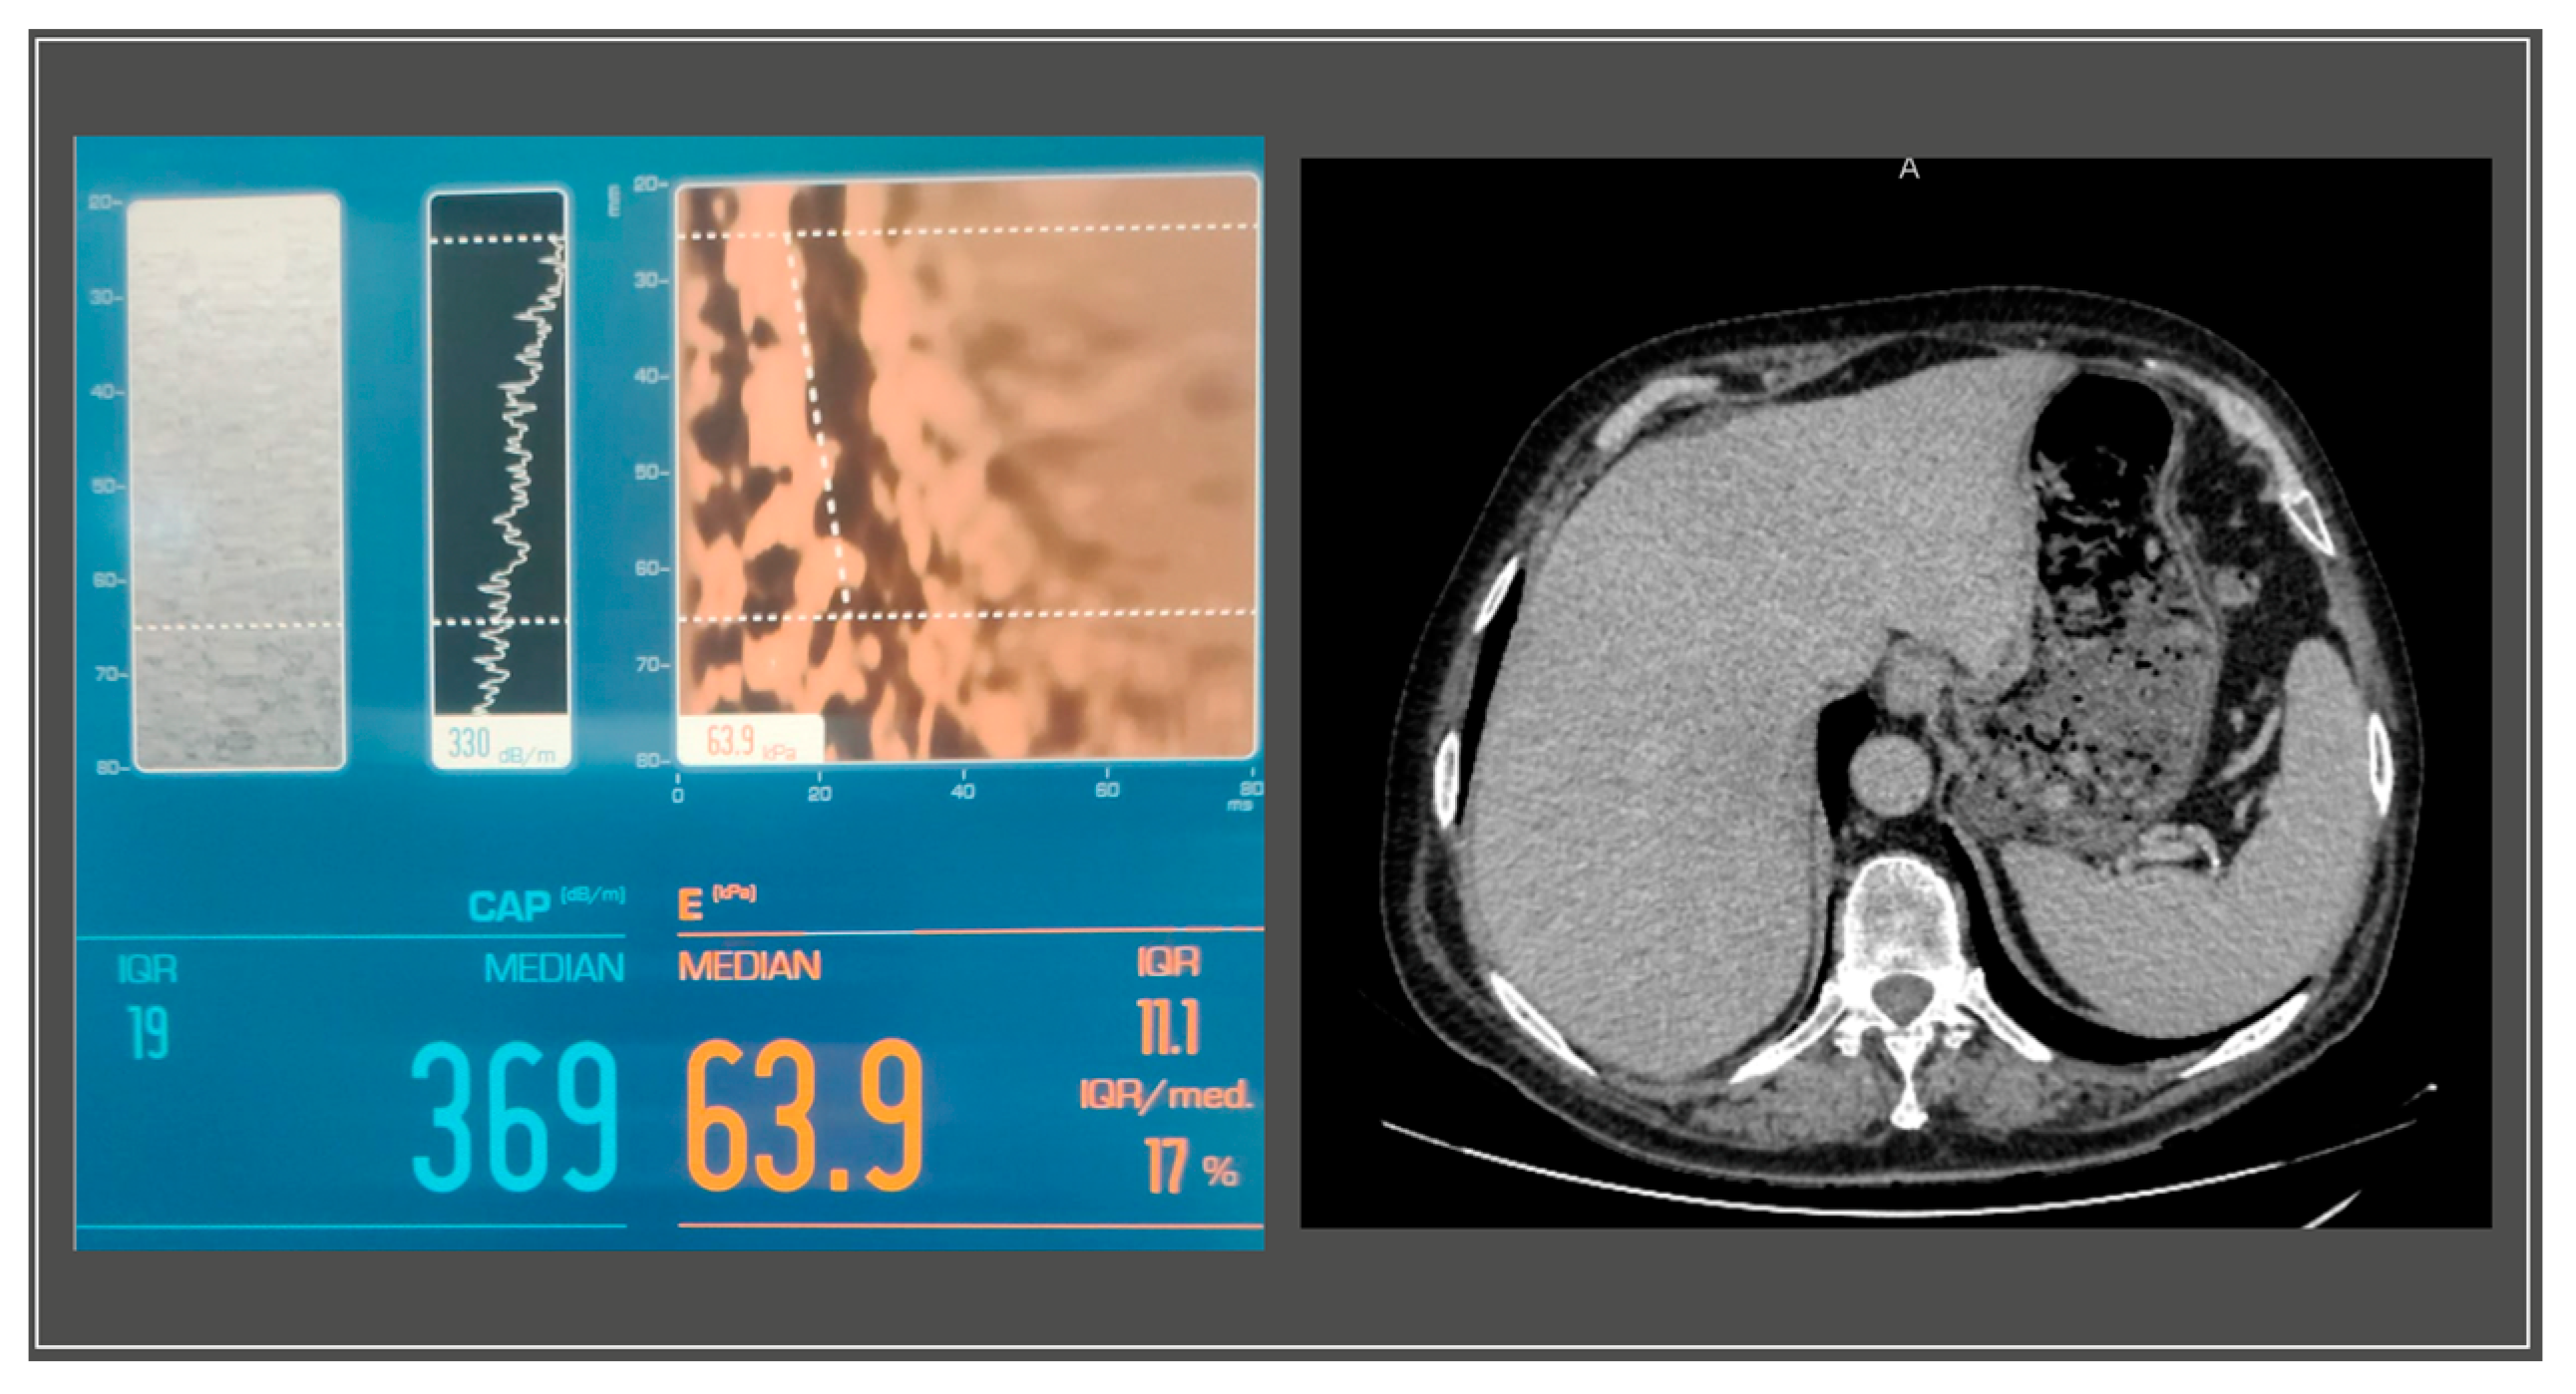

A gastroenterology evaluation was requested at the time; the abdominal ultrasound revealed a liver with a hyperechoic structure, with considerable steatosis, a nodular structure, with slightly irregular edges, an abnormal vascular system with reduced blood supply and a disrupted flow pattern in the periphery, without intrahepatic localized processes. The pancreas showed no anomalies, while the spleen was slightly increased in size, measuring 14 cm in its long axis. The further Fibroscan® test displayed stage III steatosis and grade IV liver fibrosis (S3, F4) (Figure 3).

Figure 3. Liver imaging with S3F4 score on Fibroscan® and abdominal CT with mild liver enlargement.